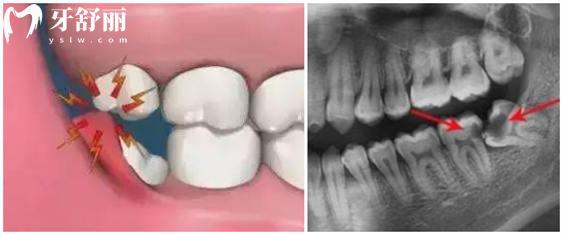

每颗牙齿一般都是有固定位置的,牙齿不齐有很多原因就是牙槽骨没有位置挤歪了其他牙齿,因此想要排齐所有的牙齿是必须要腾出空间的,因此需要拔牙,需要的空间少拔的牙齿就少,需要的空间大拔掉的牙齿数量就多。尤其是前突的错颌患者,大部分都是需要拔牙的。

牙齿矫正一般拔掉都是哪些牙齿?

1.一般的情况下拔掉的是双尖牙,对平时的牙齿使用影响不是特别大。

2.智齿,成人牙齿矫正如果智齿长出来的话,可以把智齿拔除留空间,拔掉智齿对整副牙齿是完全没有影响的。

3.坏牙,有的技术好的医生会选择正好利用已经坏掉的牙齿的位置,进行移动,需要制定个性化的方案。